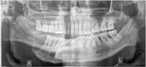

An unusual case of disappearing bone disease in the mandible and literature review

Ambareen A. Naqvi and others

Journal of Surgical Case Reports, Volume 2017, Issue 2, February 2017, rjx025, https://doi.org/10.1093/jscr/rjx025